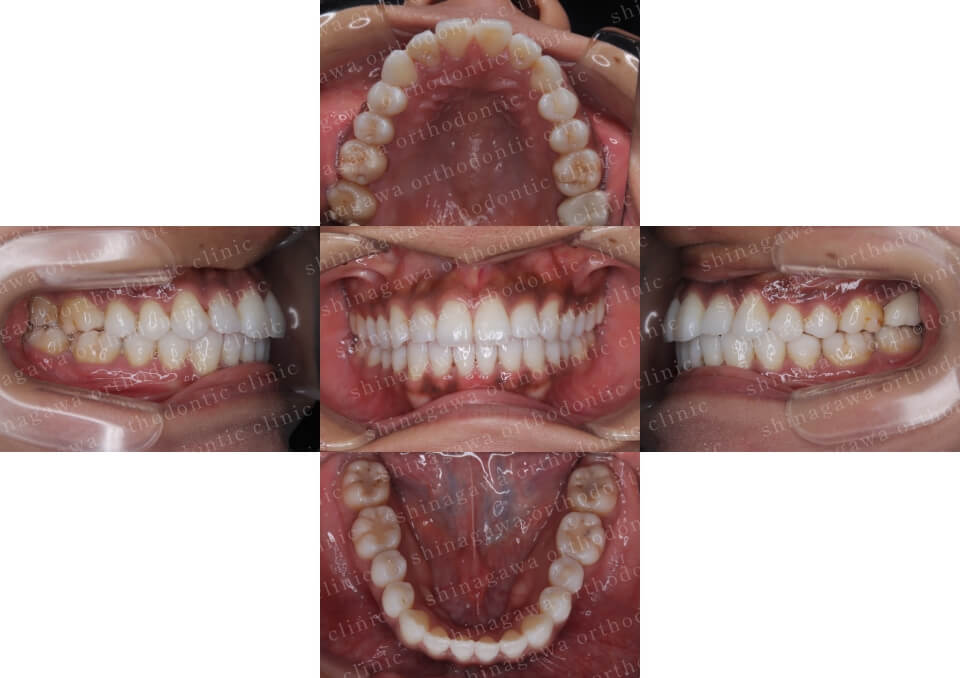

症例7

上下顎前突

| 年齢 | 25 歳 |

|---|---|

| 性別 | 女性 |

| 住所 | 神奈川県川崎市 |

| 主訴 | 出っ歯 |

| 不正咬合の種類(診断) | 上下顎前突 |

| 装置 | リンガル |

| 抜歯/非抜歯 | UR4, UL4, LR4, LL4 |

| 期間 | 32M |

| 費用 | 1,430,000 円 |

| リスク・副作用 | 矯正治療による歯の移動に伴う痛み, 虫歯, 歯肉退縮, 歯根吸収 |